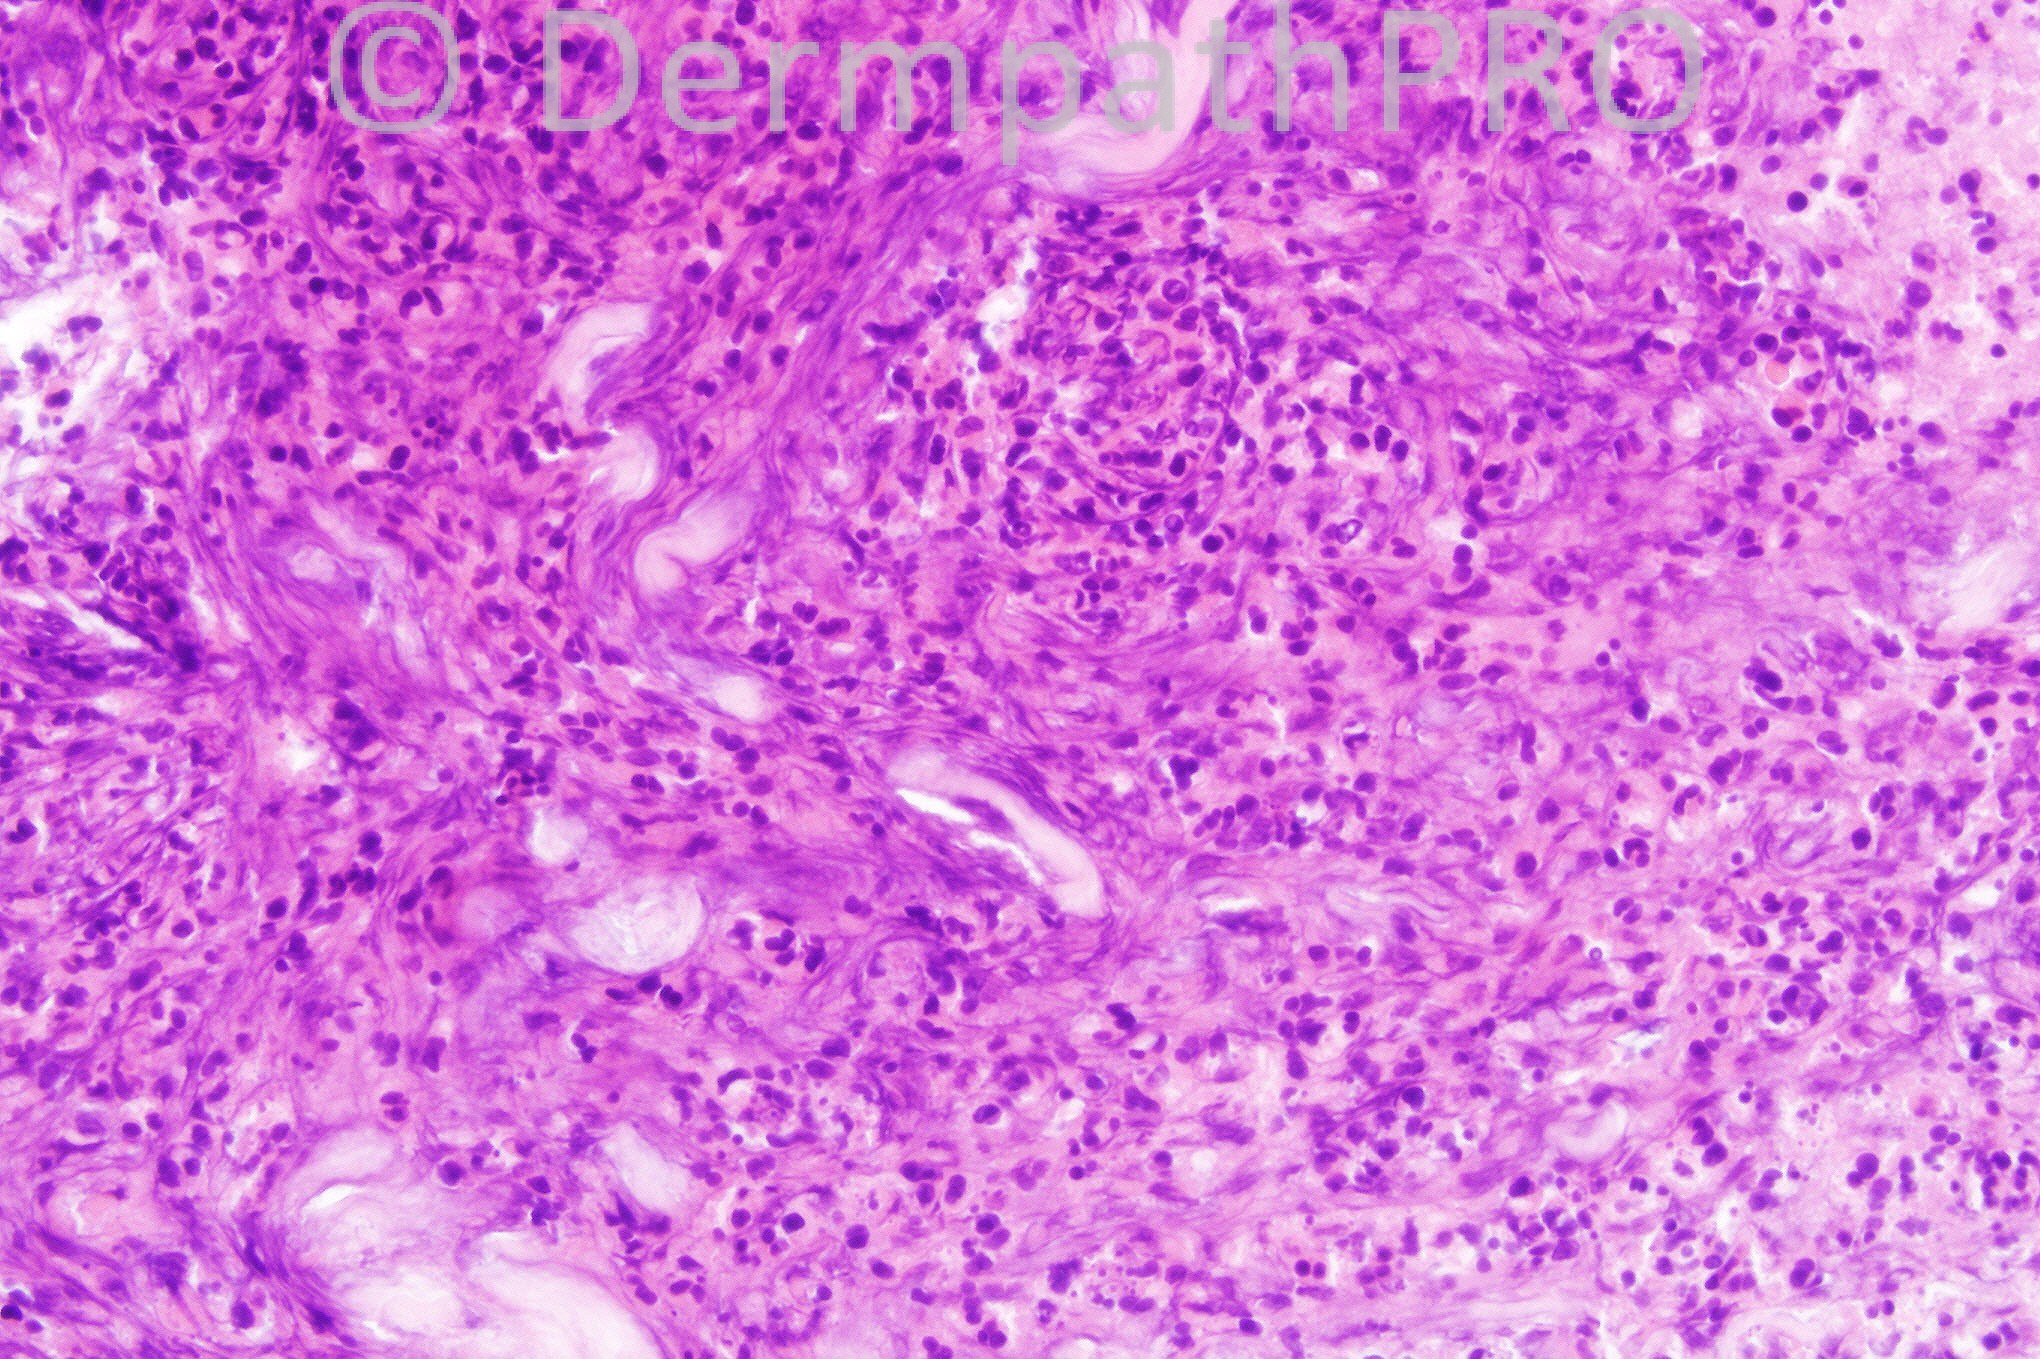

42 years-old male with erythema and edema of the hand.